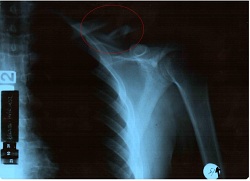

To była prosta historia. Taka, jakich wiele. Jesienny trening, niska temperatura, niedogrzane opony. Trochę za dużo gazu na wyjściu z zakrętu i nagle zamieniam się miejscami z motocyklem. Asfalt okazuje się zaskakująco szorstki. I twardy. Po chwili, gdy świat przestaje wirować w szalonym tempie, wokół zapada złowroga cisza. Głębszy oddech na uspokojenie, przewracam się na plecy i wszystko jest już jasne - obojczyk do wymiany.